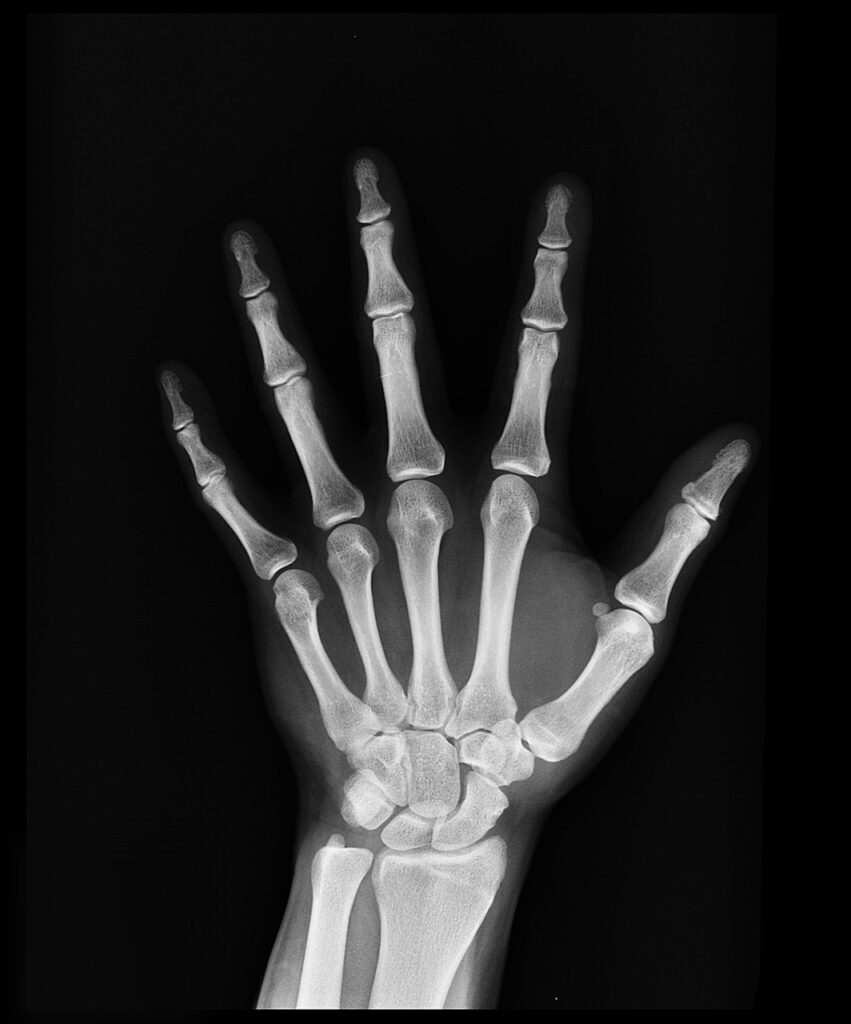

- Fractures and Bone Injuries: X-rays can clearly reveal breaks, fractures, and other abnormalities in bones.

- High Resolution: Capable of producing detailed images of bones and certain tissues.